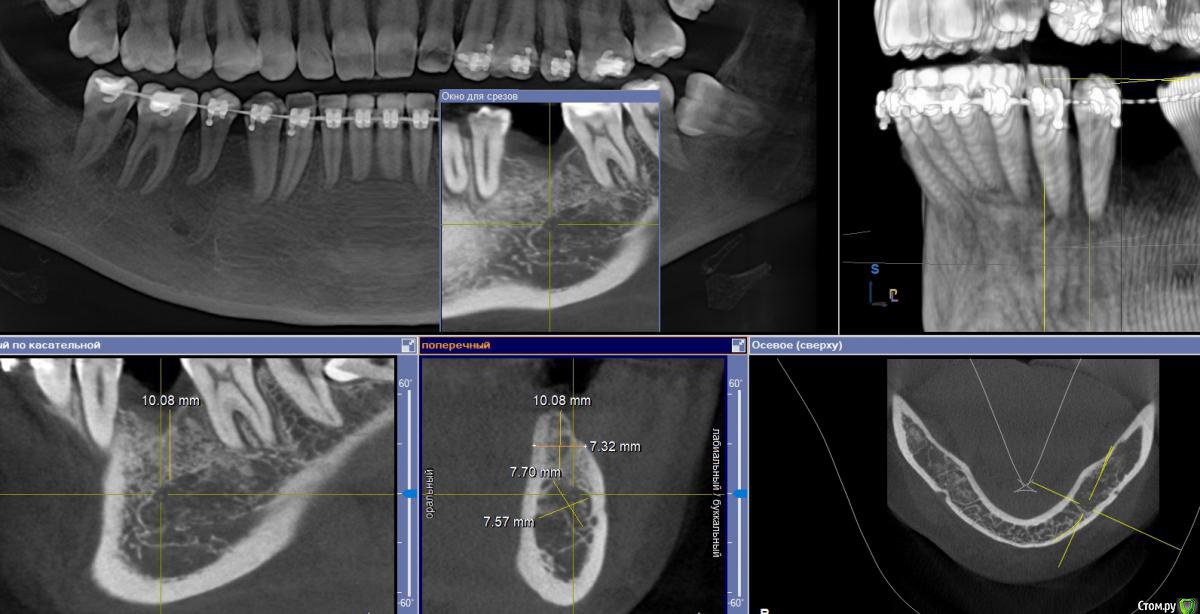

Fin Опубликовано 6 мая, 2020 Поделиться Опубликовано 6 мая, 2020 Здравствуйте коллеги. Пришла пациентка, для установки импланта в обл 3.6. После осмотра КТ обнаружил образование в проекции будущего импланта. В ходе осмотра КТ так же обнаружилось несколько подобных образований по НЧ. Помогите советом, кто сталкивался с подобной ситуацией и что это может быть? Ссылка на комментарий

Дмитрий Л. Опубликовано 6 мая, 2020 Поделиться Опубликовано 6 мая, 2020 Ну сделайте трепан биопсию. Через пару недель можно будет и имплант вкрутить. Я думаю что это костный рисунок. Ссылка на комментарий

wladdX Опубликовано 6 мая, 2020 Поделиться Опубликовано 6 мая, 2020 (изменено) Мне тоже кажется, что вы принимаете балочную структуру и петли н\ч канала за н\образование. Такое встречается иногда. Похожий случай На ОПТГ выглядит уже не так трагично Изменено 6 мая, 2020 пользователем wladdX 1 Ссылка на комментарий

It'sGeorgy Опубликовано 6 мая, 2020 Поделиться Опубликовано 6 мая, 2020 Тоже часто сталкиваюсь с таким. Костный рисунок. 1 Ссылка на комментарий

Fin Опубликовано 7 мая, 2020 Автор Поделиться Опубликовано 7 мая, 2020 Мне тоже кажется, что вы принимаете балочную структуру и петли н\ч канала за н\образование. Такое встречается иногда. Похожий случай46_1.jpg На ОПТГ выглядит уже не так трагичноОПТГ фрагмент.jpgЧестно говоря тоже думаю, что костный рисунок но смутили размеры и то что в других местах кроме этих таких явлений не наблюдается. Сейчас пациент предоставил снимок до ортод. лечения. На нем немного видно костный рисунок. Ссылка на комментарий

Fin Опубликовано 7 мая, 2020 Автор Поделиться Опубликовано 7 мая, 2020 Тоже часто сталкиваюсь с таким. Костный рисунок.Извините, хотел нажать кнопку ответа а поставил минус((.Такое тоже вижу очень часто, но смущают размеры. Ссылка на комментарий